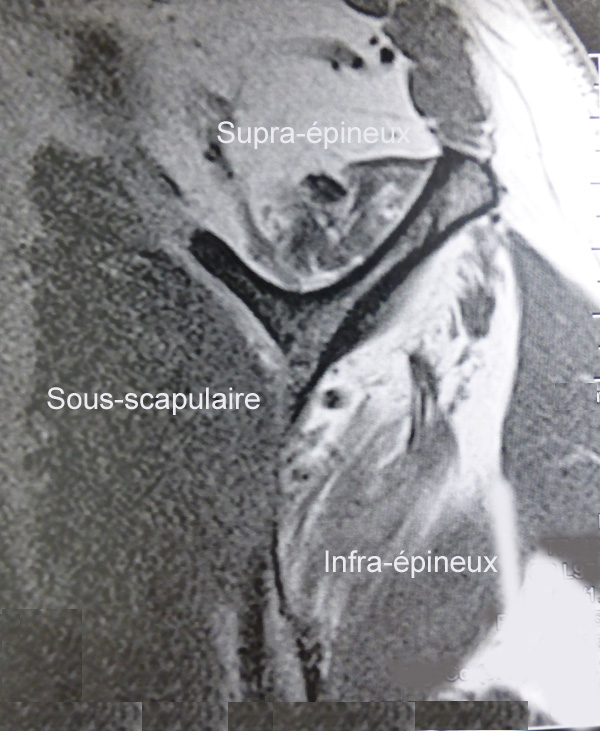

Lorsqu’un tendon est rompu, le corps musculaire s’atrophie progressivement. Cette atrophie musculaire doit être évaluée avant d’entreprendre une réparation. En effet, il serait inutile de réparer un tendon si le muscle est inactif. La qualité du corps musculaire est bien évaluée par le scanner.

- Sur ce scanner, les trois muscles de la coiffe sont très bien conservés, il n’y a pas d’atrophie ni de dégénérescence graisseuse

- Sous-scapulaire normalSupra-épineux atrophiqueInfra-épineux atrophique